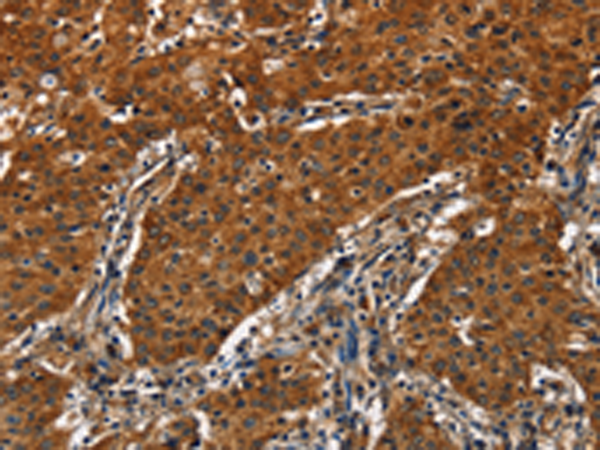

分类: 科研抗体货号: P08132别名: p67; SIGLEC3; SIGLEC-3应用: WB,IHC反应种属: Human, Mouse